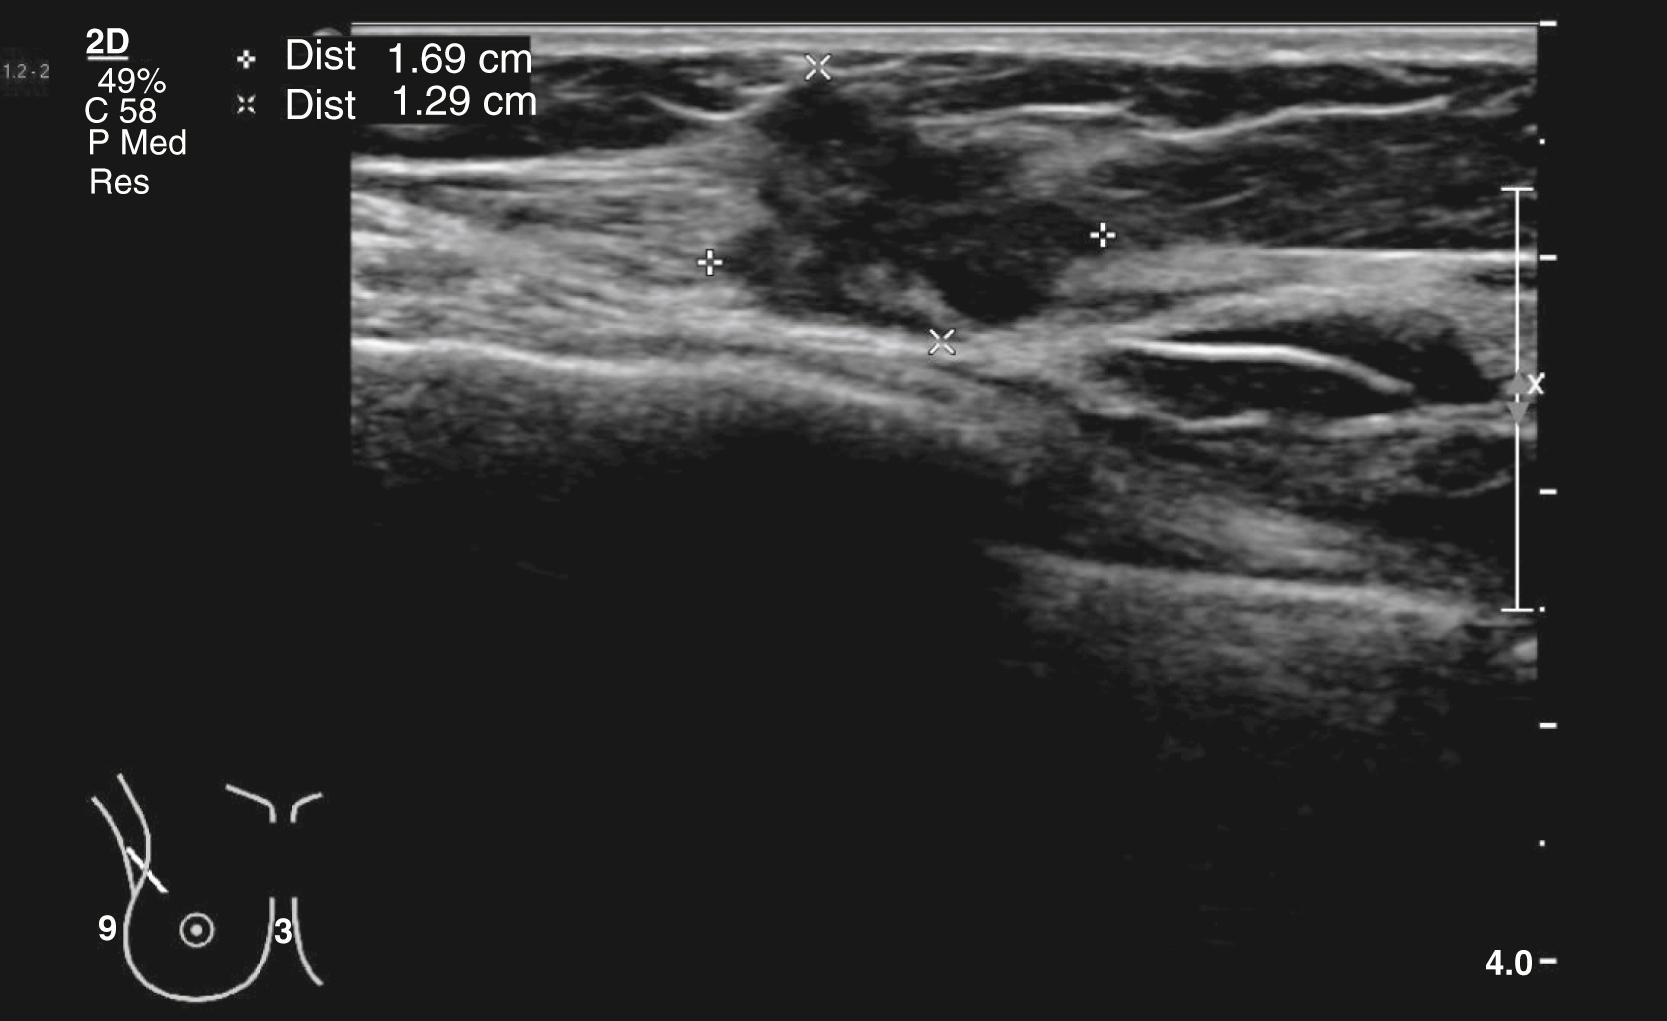

Ultrasound

High-frequency (≥10 MHz) ultrasound is the primary technique for the further investigation of focal symptomatic breast problems at all ages but is less useful for assessing the whole breast ( Fig. 20.17 ). It does not involve ionising radiation and is safe, painless and quick to perform but does require specific expertise. Under 40 years of age, it is usually the only imaging technique required. Over 40, it is usually used in conjunction with mammography if an abnormality is suspected. Ultrasound is used for guiding biopsy of both palpable and impalpable breast lesions visible on scanning. Ultrasound is also used routinely to assess the axilla in women with breast cancer. Axillary nodes that show abnormal morphology can be sampled accurately by ultrasound-guided FNA or core biopsy.

Fig. 20.17, Ultrasound scan of a dense irregular lesion due to a breast cancer.